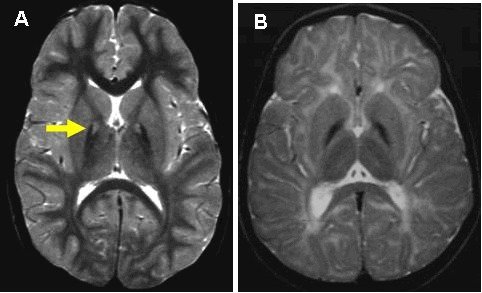

این اختلال موسوم به " PKAN"، نوعی بیماری ژنتیکی است که در اثر جهش در ژن PANK2 رخ میدهد و از هر یک میلیون نفر، سه نفر را تحت تاثیر قرار میدهد. در این بیماری که درمانی برای آن وجود ندارد، آهن در سلولهای مغز انباشته میشود و راه رفتن، بلعیدن، جویدن و فعالیتهای دیگر را برای بیماران دشوار میسازد.

پژوهشگران عقیده دارند این اختلال هنگامی رخ میدهد که نورونها، ذخیره کافی از "کوآنزیم آ" (CoA) نداشته باشند و نتوانند عملکرد معمول خود را انجام دهند. ژن PANK2، یکی از سه ایزوفرمی است که در تنظیم تولید کوآنزیم آ نقش دارد.